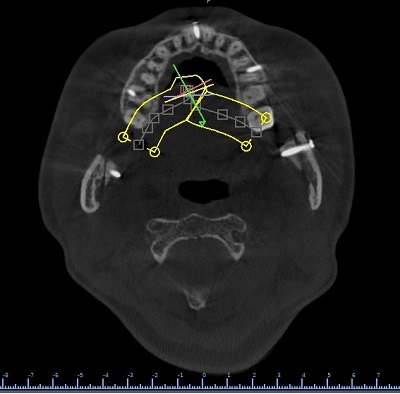

Với công nghệ 3D, bộ phận kỹ thuật sẽ xử lý file chụp từ máy X quang trên phần mềm 3D, tách các mô, xương, ...

Máy in 3D in ra mẫu xương với tỷ lệ hoàn toàn chính xác như xương thật. Bác sĩ sẽ tiến hành đo đạc, lên phương án phẫu thuật, thực hiện trước trên mẫu xương 3D.

Ảnh 3D sau phẫu thuật

Việc phẫu thuật với mẫu xương 3D không những làm giảm rất nhiều thời gian phẫu thuật thật mà còn đảm bảo độ chính xác gần như tuyệt đối, tránh sai sót trong quá trình phẫu thuật.

Xương hàm sau phẫu thuật